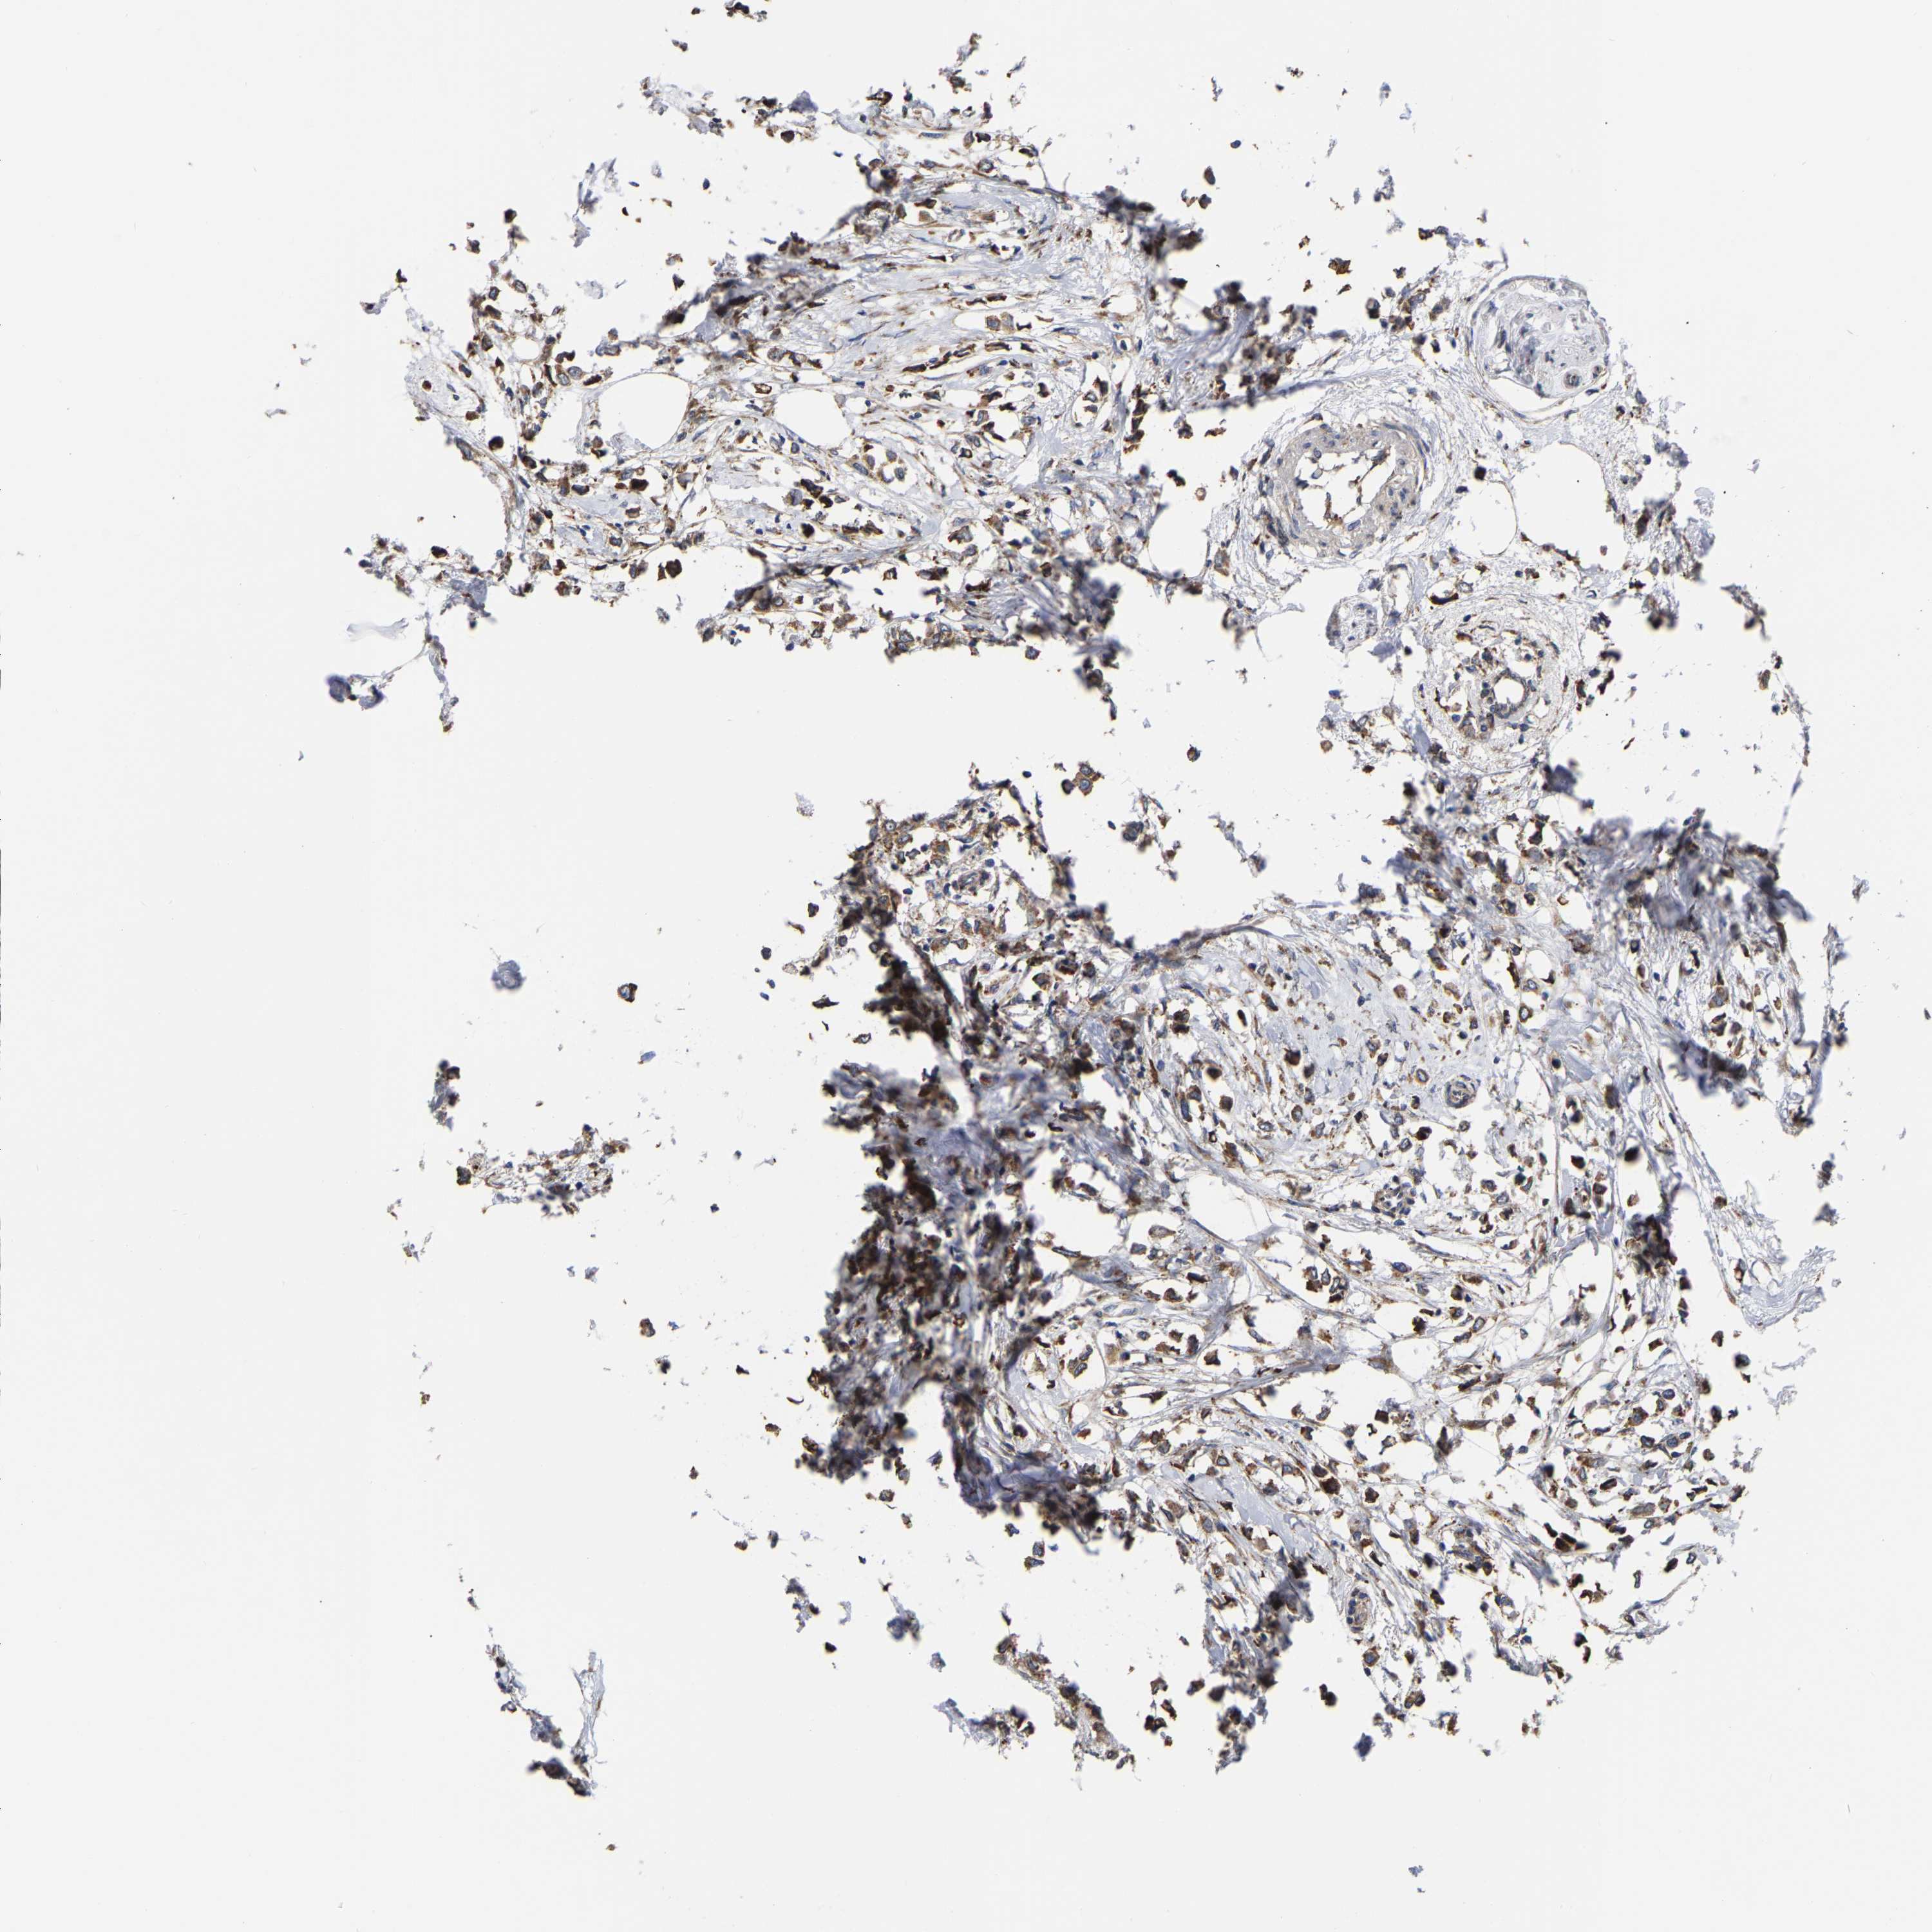

CANCER BREAST CANCER Show tissue menu

BRCA TCGA BRCA VALIDATION PROTEIN EXPRESSION